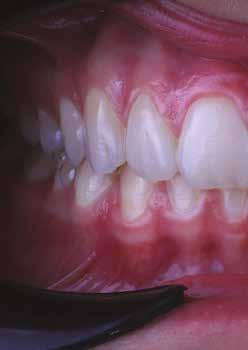

A fogászati kezelések során manapság már nem kizárólag az esztétikai megjelenés helyreállítására törekszünk. Sokszor a kedvezőtlen esztétikai megjelenés hátterében álló okok következményes módon a fogazat funkcionális működését is károsítják, így a kezelések során ezeknek a helyreállításával is foglalkoznunk kell. A különböző funkcionális és esztétikai diszkrepanciák kezelésére számtalan módszer létezik, ám ezen fogászati beavatkozások mindegyikében közös, hogy a kivitelezésük során nagyon szoros együttműködésre van szükség a kezelést végző fogorvos és a munkáját segítő fogtechnikus között. Az alábbi esetbemutatás során egy fiatal hölgypáciens fogazatának héjak alkalmazásával történő esztétikai és funkcionális rehabilitációját szeretnénk ismertetni.

A 19 éves hölgypáciens azzal a kéréssel jelentkezett a rendelőnkbe, hogy szebb fogakat szeretne. Az első konzultáció alkalmával megkérdeztük, hogy mi zavarja leginkább a fogazatának jelenlegi megjelenésében, valamint azt is megbeszéltük vele, hogy milyen végeredmény elérése esetén lenne maradéktalanul elégedett. Ebben az esetben a kezelési célokat az alábbiakban határoztuk meg:

A páciens fogazata esztétikai megjelenésének és funkcionális működésének a lehető legtöbb, saját foganyag megtartása mellett történő helyreállítása (1. és 3. ábra).

A lehető legideálisabb esztétikai végeredmény elérése érdekében néhány esetben a fogak alakjának módosítá -